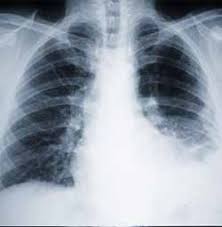

Once asbestos fibers are released into the air, they can either be inhaled or ingested by a human. At this point, the fibers can travel to any one of the main linings of the body. The pleura is a lining that surrounds and protects the lungs. If the asbestos fibers travel and lodge into this lining, a person will develop pleural mesothelioma. The peritoneum is a lining that surrounds and protects the abdominal cavity. If asbestos is ingested and travels to this delicate covering of the abdominal viscera, peritoneal mesothelioma will begin to develop. Finally, the third type of mesothelioma is pericardial mesothelioma. This cancer results when asbestos fibers lodge in the pericardium, or protective covering of the heart. Once the fibrous pieces of asbestos travel to any one of these major linings, they will become lodged and begin to produce carcinogenic scar tissue. At that point, mesothelioma is well on its way to causing numerous health problems.

The dormancy period of all types of mesothelioma is extremely long. This means that the time from exposure to the fibers until the appearance of symptoms can be anywhere from twenty to fifty years long. This fact makes treating mesothelioma extremely challenging because the cancer has normally progressed too far by the time of discovery. Also, the symptoms that come with each type of mesothelioma are similar to the symptoms that other major illnesses and diseases have as well. Most time, mesothelioma is misdiagnosed due to these symptom similarities. For example, pleural mesothelioma may cause shortness of breath, coughing, wheezing, exercise intolerance and chest pain. These symptoms are the same symptoms that many major respiratory diseases cause as well. Chronic obstructive pulmonary disease, asthmatic bronchitis and emphysema all carry the same symptoms as pleural mesothelioma.